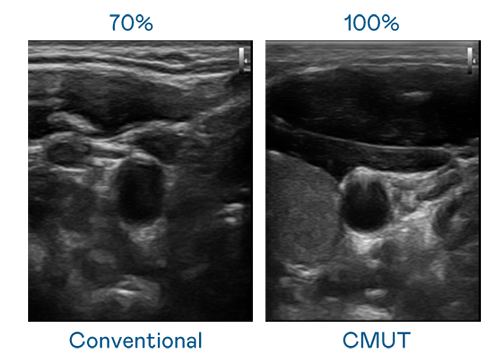

CMUT 技术是一种用电容式微机电元件来产生超音波讯号的技术。与传统 PZT 压电式技术相比,CMUT 频宽增加 30%,更宽频的超音波讯号让影像解析度大幅提升,是实现高影像品质医疗超音波扫描、促进精准医疗发展的关键技术。

超音波影像的解析度高低,首先取决于探头能发出的讯号频宽。华体汇官网登录入口 CMUT 可提供高清晰的超音波讯号,提供高频宽、高灵敏度、影像纹理细节更高的超音波影像,协助医护人员缩短影像判读时间及利用精准的医疗影像进行诊断。